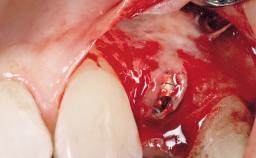

Late Placement of an Implant in a Maxillary Left Central Incisor Site

A 36-year-old female patient was referred for the replacement of the upper left central incisor (tooth 21), which had fractured. Although the tooth had been asymptomatic for many years, the crown began to loosen, at which time she presented to her dentist for an assessment. Teeth 21 and 22 had both been endodontically treated many years previously. She was a healthy individual and a non-smoker.

Bone Augmentation Horizontal|Staged

Augmentation Materials Xenogenous|Membrane

Bone Volume Deficient horizontally, requiring prior grafting